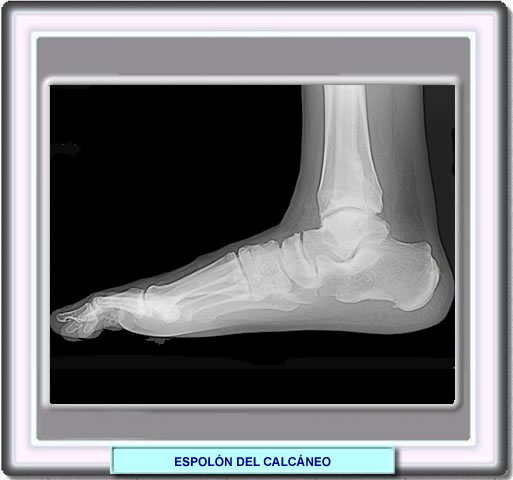

Espolón Calcáneo